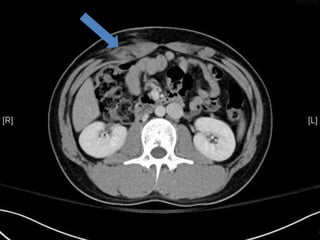

• FAST / abdominal CT >internal bleeding/emergent OP indication

• CT:

 Shanmuganathan(2004)

 Sen:97%, spe:98%, accuracy:98% in penetrating stab wds

 Velmahos(2005)

 GSW: Sen 90.5, Spe: 96%

Radiology 2004:231:775-784

J trauma 2005:59:1155-1161